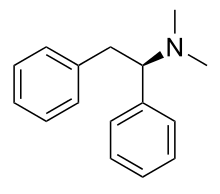

The pharmacodynamic response to an opioid depends upon the receptor to which it binds, its affinity for that receptor, and whether the opioid is an agonist or an antagonist. For example, the supraspinal analgesic properties of the opioid agonist morphine are mediated by activation of the μ1 receptor; respiratory depression and physical dependence by the μ2 receptor; and sedation and spinal analgesia by the κ receptor. Each group of opioid receptors elicits a distinct set of neurological responses, with the receptor subtypes (such as μ1 and μ2 for example) providing even more [measurably] specific responses. Unique to each opioid is its distinct binding affinity to the various classes of opioid receptors (e.g. the μ, κ, and δ opioid receptors are activated at different magnitudes according to the specific receptor binding affinities of the opioid). For example, the opiate alkaloid morphine exhibits high-affinity binding to the μ-opioid receptor, while ketazocine exhibits high affinity to ĸ receptors. It is this combinatorial mechanism that allows for such a wide class of opioids and molecular designs to exist, each with its own unique effect profile. Their individual molecular structure is also responsible for their different duration of action, whereby metabolic breakdown (such as N-dealkylation) is responsible for opioid metabolism.

Anilidopiperidines